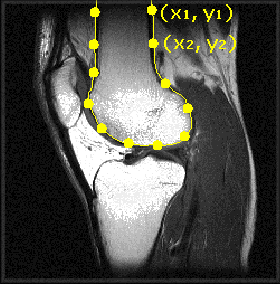

Figure: Landmark identification and mark-up in medical images